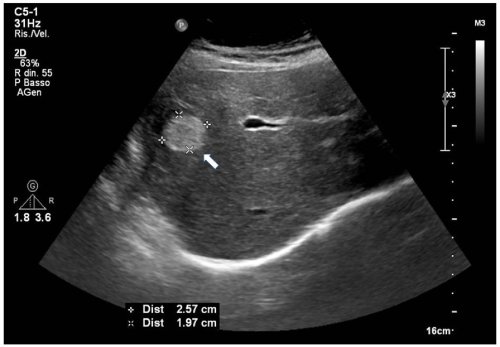

- Siêu âm: thường là khối tăng âm tương đối đồng nhất, bờ rõ (có thể thay đổi ở u không điển hình).